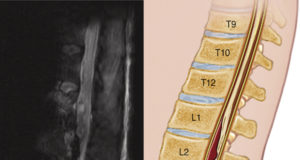

Changing the game in knee osteoarthritis: A vascular approach

Chinmaya Shelgikar, MD, discusses the benefits of vascular surgeons performing geniculate artery embolization.

Geniculate artery embolization (GAE) is an intra-arterial, catheter-based procedure used to treat chronic...